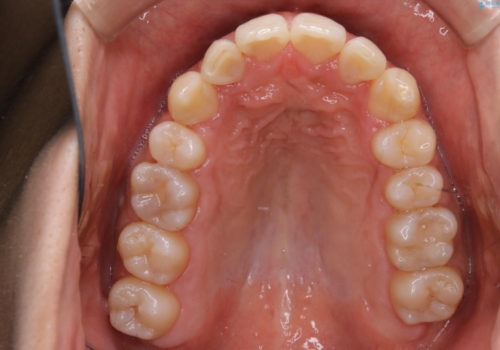

一見、表面はそこまで汚れが付着していないようにみえますが、裏面を見てみると、着色や歯石が多く付着していました。個人差はありますが、3カ月に1回の来院でもここまで汚れが付着する為、メンテナンスやクリーニングは、3ヶ月に1回をおすすめします。